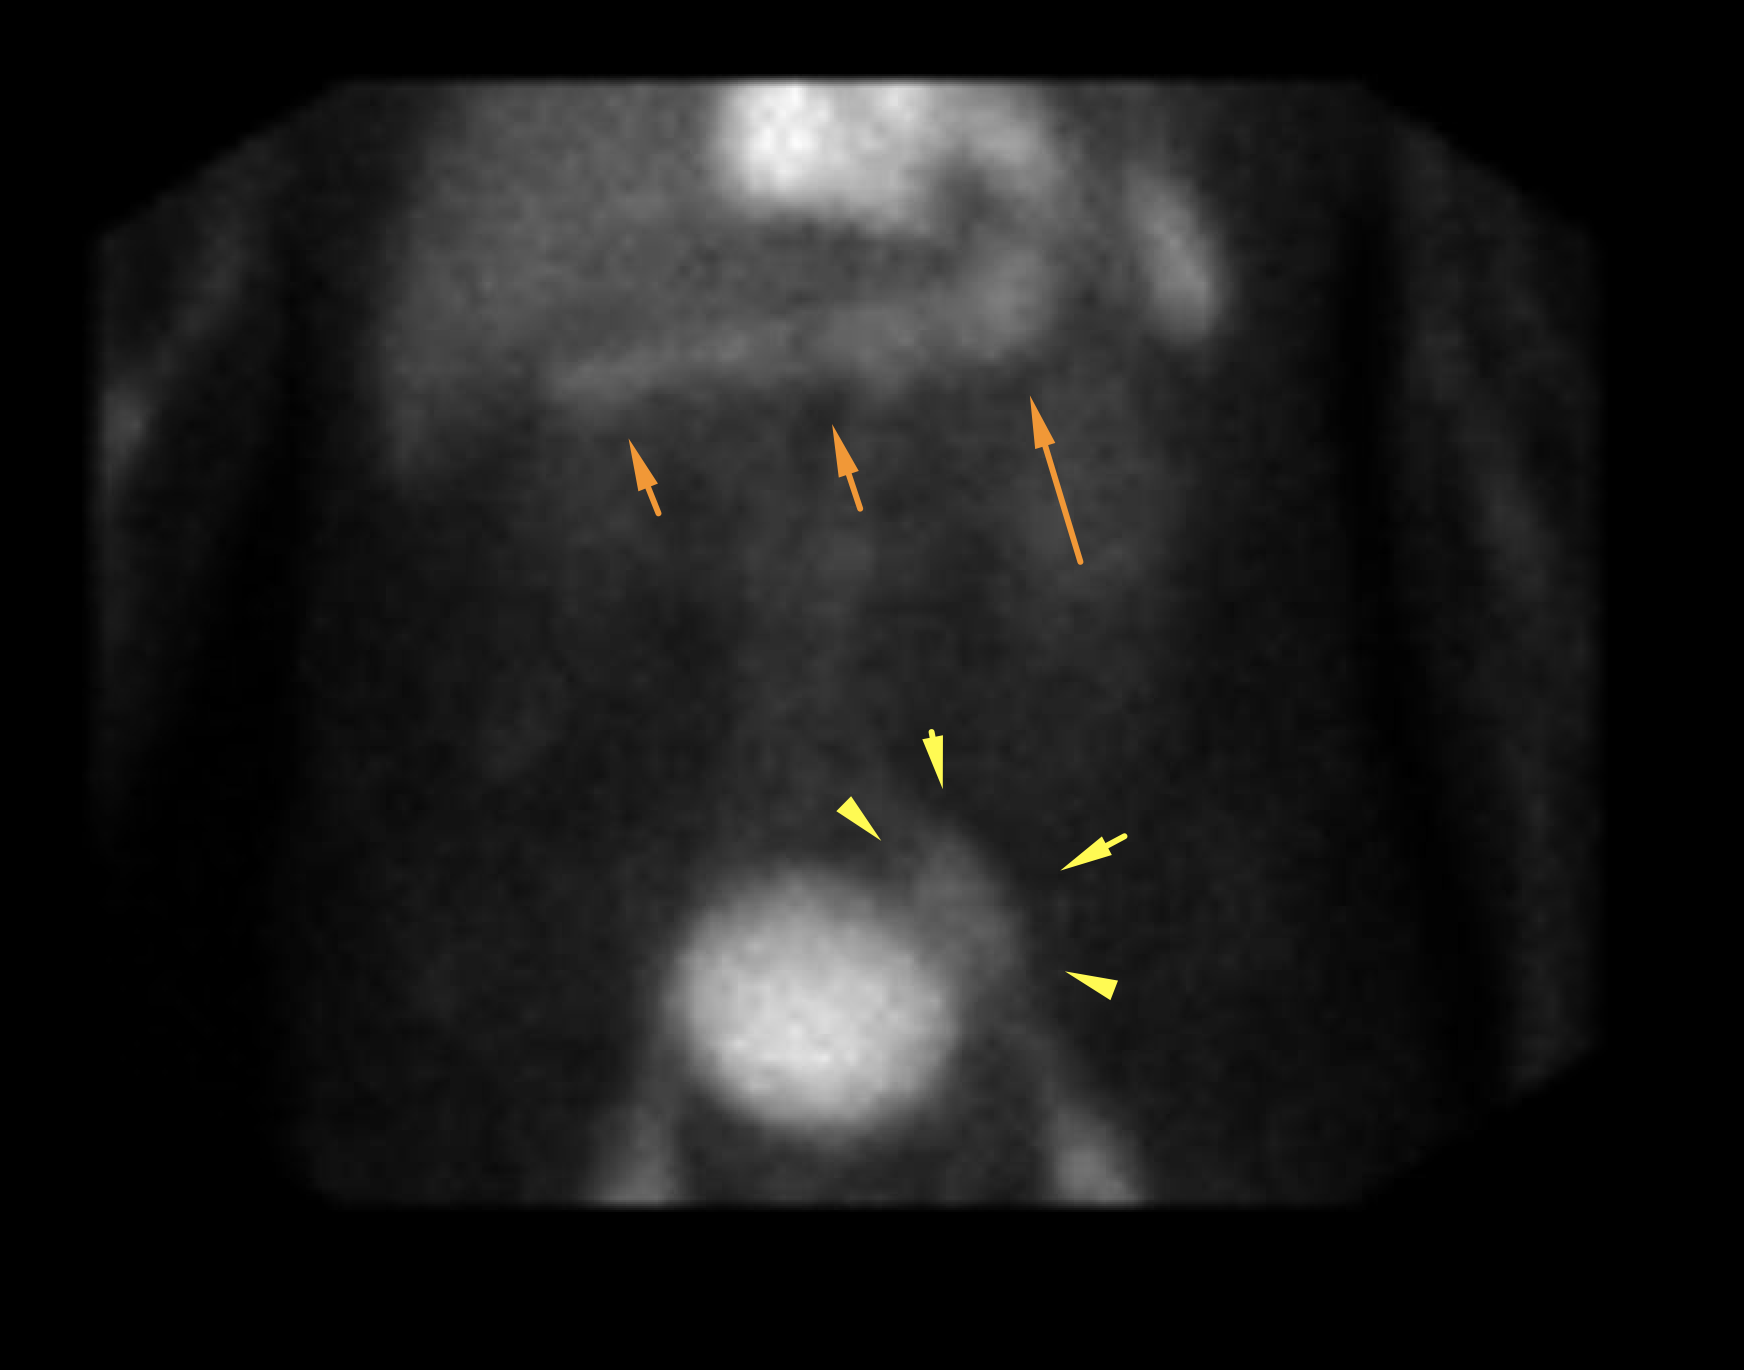

Age: 89

Sex: Male

Indication: GI bleeding

Radiotracer: Tc99m labeled RBCs

Sample ReportNo evidence of active GI bleeding during the course of this study.